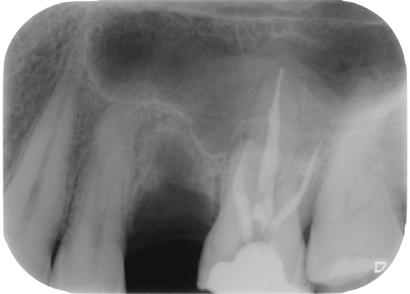

1. ábra: Kiindulási röntgen. A felső nagyőrlőfog trepanálását akut beavatkozásként egy másik rendelőben végezték.

Az endodonciai ellátás a trepanációs nyílás kialakításával kezdődik. Ez a lépés biztosítja a gyökércsatorna bemeneti nyílások könnyű lokalizál-

hatóságát, a csatornák kézi tűkkel való szondázhatóságához szükséges megfelelő hozzáférést, valamint a gyökércsatornák feltágításához, tisztításához és a gyökértömés elkészítéséhez szükséges kiindulási

feltételeket. A trepanációs nyílás kialakítására vonatkozó szabályok meghatározzák, hogy ez a nyílás milyen formával és mérettel kerül kialakításra, valamint azt is, hogy a gyökércsatorna-bemenetekhez képest hol helyezkedik el. Ez a kezdeti fázis jelentős mértékben meghatározza az ezt követő lépések lehetséges sikerességét. Kijelenthető, hogy az endodonciai ellátás sikeressége nagymértékben függ a trepanációs nyílás megfelelő kialakításától [1–3]. Ha a trepanációs nyílás nem megfelelő pozícióban, mélységben, vagy kiterjedésben kerül kialakításra, akkor az ezt követő terápiás lépések során joggal számíthatunk komplikációk megjelenésére. Megnehezíthetik, vagy bizonyos helyzetekben lehetetlenné tehetik a gyökércsatorna-bemenetek lokalizálhatóságát, a csatornák mechanikai tisztítása során a nikkel–titán (Ni–Ti) gyökérkezelő tűkben fraktúrák kialakulásához vezető nagyságú erők ébredhetnek, sőt akár a megmaradt dentinállo -

2. ábra: A hozzáférési nyílás kialakítása során túlzott mértékű ép foganyag eltávolítása történt mesiobukkális és apikális irányba.

– 3. ábra: A visszamaradt nagy méretű pulpakő teljes mértékben elzárja a palatinális csatornabemenetet. – 4. ábra: A gyökértömés behelyezése előtt látható állapot. A csatornák feltágítása és tisztítása befejeződött.